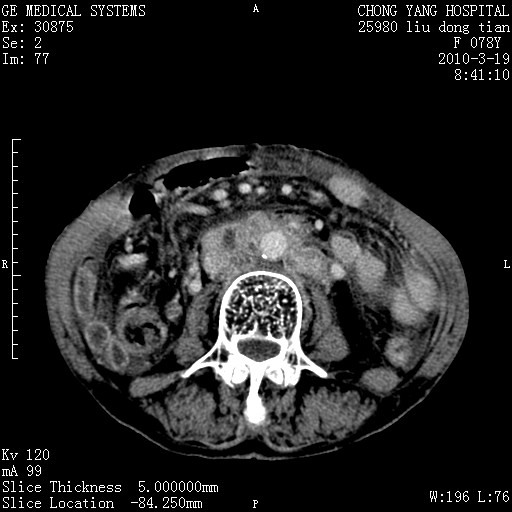

标题: CT25199:F 78Y 腹胀半年 消瘦乏力 [打印本页]

胆囊壁增厚并明显强化,胆囊癌伴多发转移瘤可能性大,淋巴瘤不除外,右肾囊肿,胸腹水.

考虑nhl,肝、脾、腹膜腔及腹膜后多发淋巴结受侵,腹水,右肾囊肿,慢性胆囊炎,右侧少量胸腔积液。

胰头有肿块形成,胰头ca伴肝脾、腹膜腹膜后转移

胆囊有软组织影有强化,支持胆囊癌,肝脾、腹膜后淋巴结转移。

nhl的淋巴结多围绕主动脉,而且主动脉会移位,所以不考虑nhl。

分开来讲:肝左叶、尾叶病灶有不均强化像肝癌;

肝门、胰腺头、腹膜后多个团块: 淋巴瘤,转移;

一元论最好了 淋巴瘤所致改变; 胆囊癌转移不像,胆囊周围肝组织清晰,肝癌淋巴结转移?三元论都不止。

最后报的胰头癌多发转移,脾脏单独考虑囊肿或淋巴管瘤。